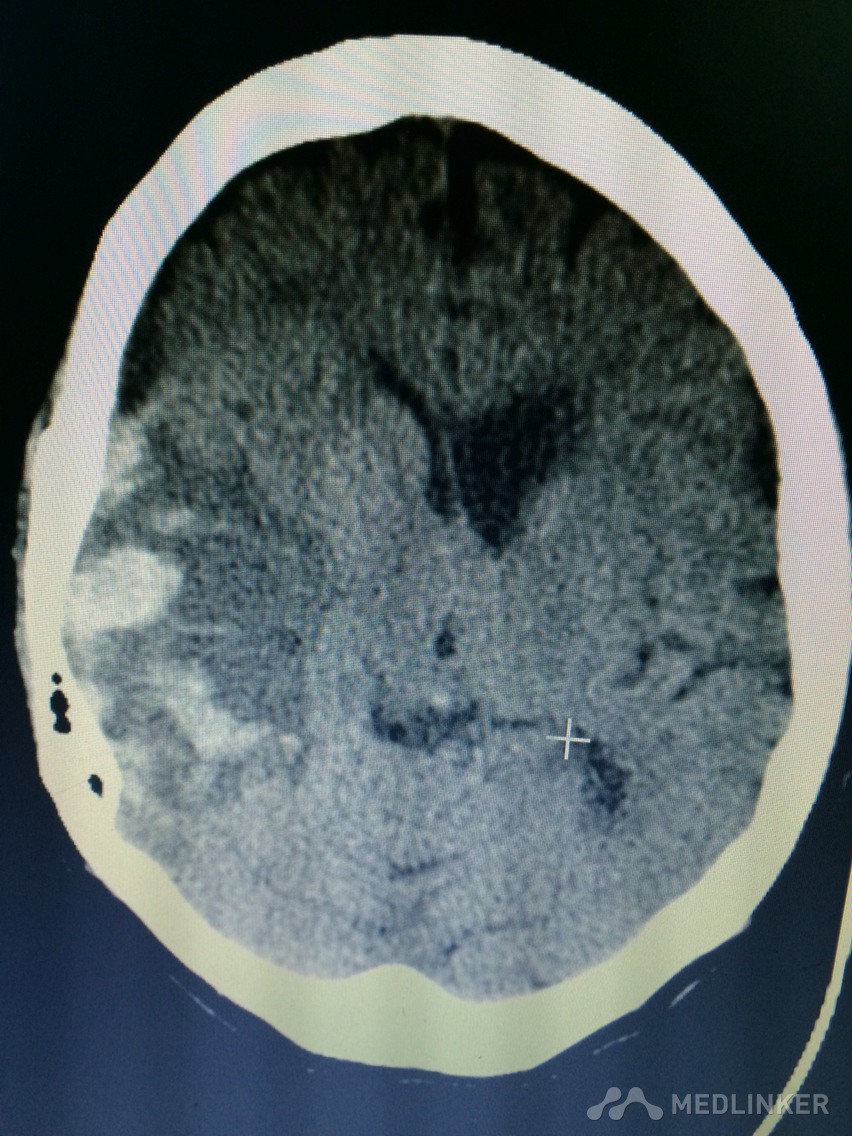

下面的CT考虑?

1天前,患者睡醒后出现反应迟钝,认知功能障碍,左侧肢体乏力。 既往无高血压病史,近期无外伤史。